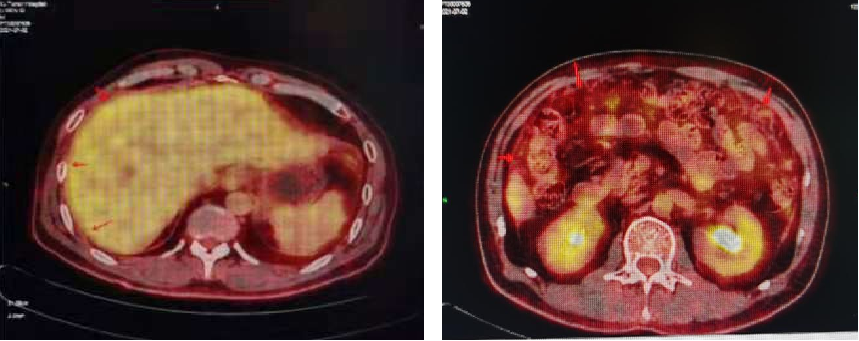

肝周少量积液,肝缘腹膜增厚,大网膜絮状增厚,轻度FDG代谢,考虑腹膜转移。